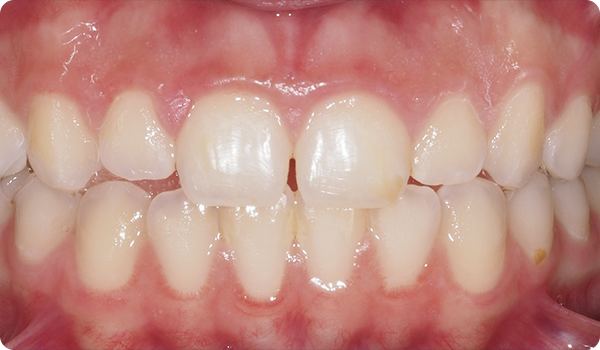

De praktijk stuurt drie foto's en het STL-bestand van een scan via Corus Link om de casus te beoordelen.

Met Right krijgen je patiënten de glimlach die ze willen in de tijd die ze willen, op een comfortabele en onopvallende manier.

Het uitlijnen van de tanden met Right is de perfecte en meest conservatieve basis voor toekomstige whitening of fineerbehandelingen die de glimlach van de patiënt perfect maken.